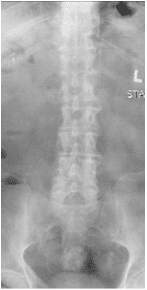

X-rays and MRI of the Lumbar spine showed L4-5 degenerative spondylolisthesis

and severe spinal stenosis.